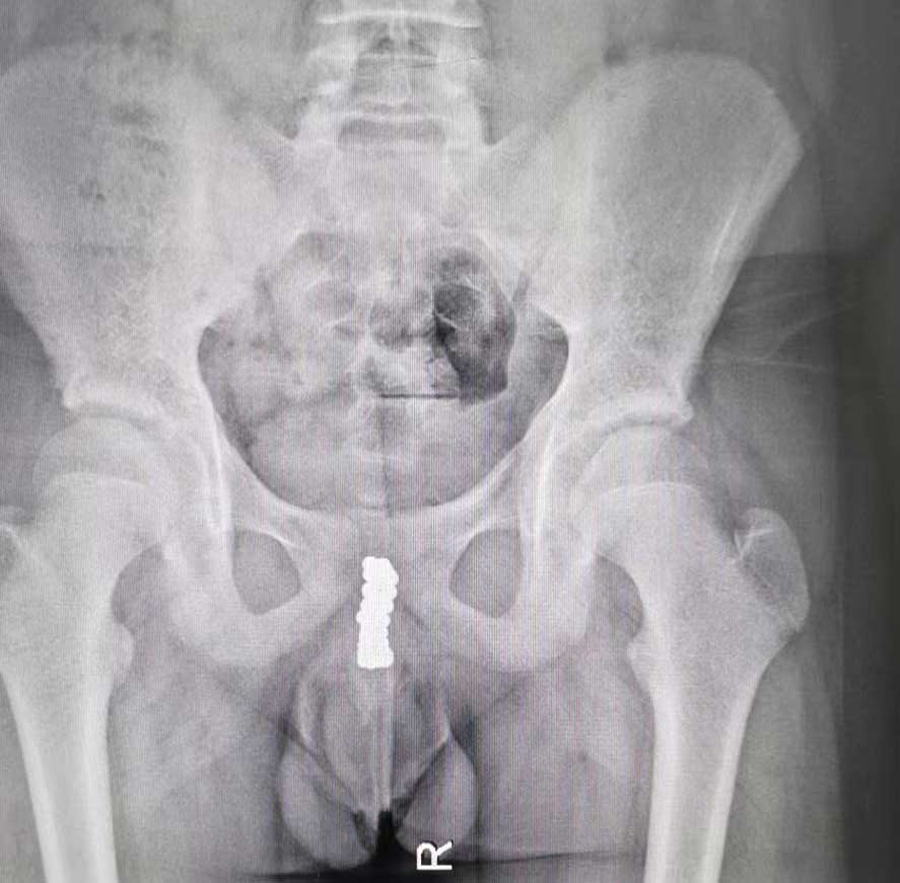

病例1:膀胱、尿道取出近50颗磁力珠

“孩子说把磁力珠塞进尿道里了。”家长一句话让在场人大吃一惊。果然,医生查体时,在小宇会阴区域摸到了珠子。CT检查同样证实尿道内有珠子样的异物,并且吸附在一起。在医生的追问下,小宇才满眼含泪地说了实话。原来,出于好奇,他趁家长不注意,将磁力珠一颗一颗塞进尿道口,并没告诉家长,等出现排尿疼痛、血尿后,才不得不跟家长说起。由于磁力珠位于后尿道膜部位置,所以医生从后尿道位置剖开,手术取出10余颗磁力珠。术中,C型臂透视显示,膀胱内还有一团磁力珠,医生通过下腹部耻骨联合上的切口,将膀胱打开,又取出30多颗磁力珠。手术前后近3个小时,共取出近50颗磁力珠。由于磁力珠在尿道及膀胱内的长时间吸附,取出时附着着脓性分泌物,说明尿道内已经感染了。

“好在及时取出,避免了对尿道黏膜的进一步损伤及远期膀胱功能受损的可能。”泌尿外科副主任医师谢方达说。术后,经过对症治疗,小宇很快痊愈出院了。